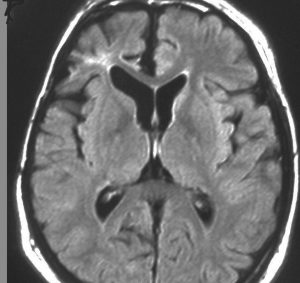

成人ののう胞性頭蓋咽頭腫 cystic craniopharyngioma です。腫瘍の周囲の視床下部に浮腫があります。右視索から内包への浮腫も顕著でした。このために認知機能障害で発症しました。この視床下部性の認知機能障害は可逆的で,手術で視床下部損傷をしないように腫瘍摘出すると認知機能は正常に戻ります。